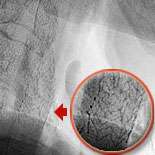

The cutting edge treatment is to insert a carotid filter balloon which is an umbrella like device used to catch debris as the artery is being opened. Fig.1 shows Ralph's narrowing of the left carotid artery. Fig.2 shows the device being inserted in Ralph's artery. In fig.3 the carotid balloon's up showing inflation of the balloon which opens the blocked artery. A stent (fig.4) which is a metallic cage is placed in the artery to keep it opened.